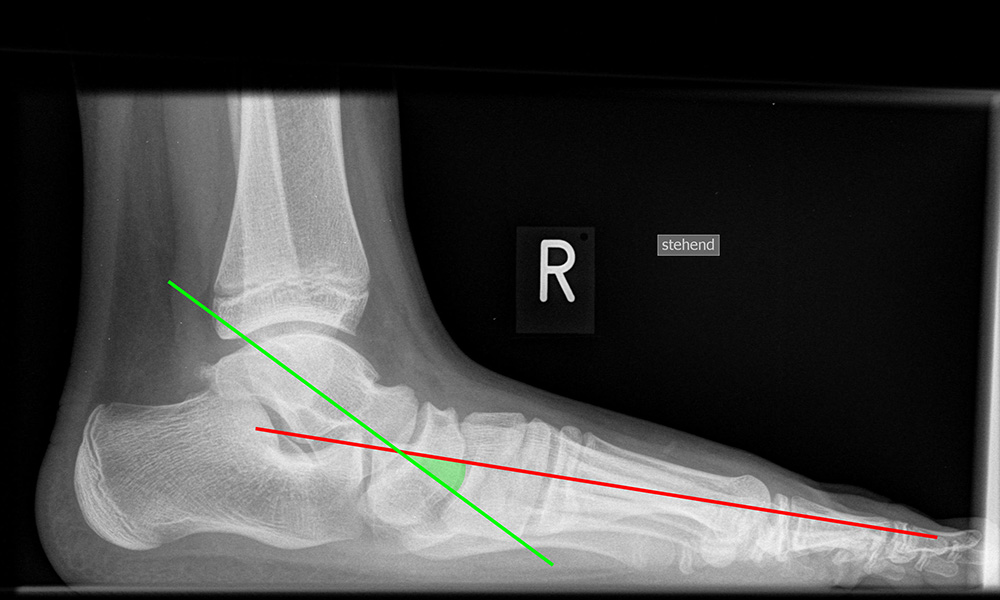

Beurteilung von Fehlstellungen des Mittel- und Rückfußes

Zur Vollansicht und zum Lesen der Bildbeschreibung bitte die Bilder anklicken.

Achsen auf der lateralen Aufnahme

Die Grundlinie (blau) ist definiert durch den tiefsten Punkt der Sesambeine und den tiefsten Punkt des Kalkaneus.

CPA (Calcaneal pitch angle): Der Kalkaneus Inklinationswinkel liegt zwischen der Grundlinie (blau) und der plantaren Begrenzung des Kalkaneus (grün) (Norm 20,8 ± 4,1° 11, 15-39° (Zwipp 2014)).

LTCA (Lateral talocalcaneal angle): Der laterale talokalkaneare Winkel liegt wird gebildet aus der Talusachse (türkis) und einer Verbindungslinie zwischen dem Oberrand des Proc. ant. Calcanei und der dorsalen Begrenzung des Kalkaneus (gelb). (Norm: 33° Range 25-45°) 1213).

LTMA (Lateral talometatarsal angle, Syn. Meary’s angle): Der laterale talometatarsale Winkel wird gebildet aus der Achse des Os metatarsale I (rot) und der Achse des Talus (türkis). (Norm: 7,1 ± 10,8 11).

Böhler-Winkel (Syn. Tubergelenkwinkel)

Es wird eine Linie vom Proc. ant. calcanei zur dorsalen Facette des Subtalargelenks gezogen (rot). Die zweite Linie verläuft von der kranialen Begrenzung des Tuber calcanei zum Subtalargelenk (gelb). Gemessen wird der nach dorsal offene Winkel zwischen den beiden Linien (Norm: 22-48° 9).

Meary’s angle dorsoplantar (Talo-Metatarsale-I-Winkel)

Der Talo-Metatarsale-I-Winkel wird auf den belasteten dorsoplantaren und lateralen Aufnahmen bestimmt. Es wird jeweils die Achse durch den Talushals gelegt (grün) und der Winkel zur Achse des Os metatarsale I bestimmt (rot). Der Winkel liefert keine Information darüber, an welcher Stelle sich die Fehlstellung befindet. Auch kann ein Serpentinen-Fuß „physiologische“ Werte liefern, da Os metatarsale I und Talushals parallele Achsen aufweisen, obwohl eine erhebliche Fehlstellung vorliegt 11. (Norm: 7,7 ± 8,2° 11).

Meary’s angle lateral (Talo-Metatarsale-I-Winkel)

Der Talo-Metatarsale-I-Winkel wird auf den belasteten dorsoplantaren und lateralen Aufnahmen bestimmt. Es wird jeweils die Achse durch den Talushals gelegt (grün) und der Winkel zur Achse des Os metatarsale I bestimmt (rot). Der Winkel liefert keine Information darüber, an welcher Stelle sich die Fehlstellung befindet. Die Fehlstellung kann das Talonaviculare-Gelenk (TN-Gelenks), das Naviculocuneiforme-Gelenk (NC-Gelenks) oder des Tarsometatarsale-I-Gelenk (TMT-I-Gelenks) betreffen, bzw. auch mehrere Gelenke einbeziehen. Der Talo-Metatarsale-I-Winkel gilt als zuverlässigster Parameter in der Differenzierung symptomatischer Pes planovalgus-Deformitäten gegenüber einer Kontrollgruppe 11.  (Norm: 7,1 ± 10,8 11).